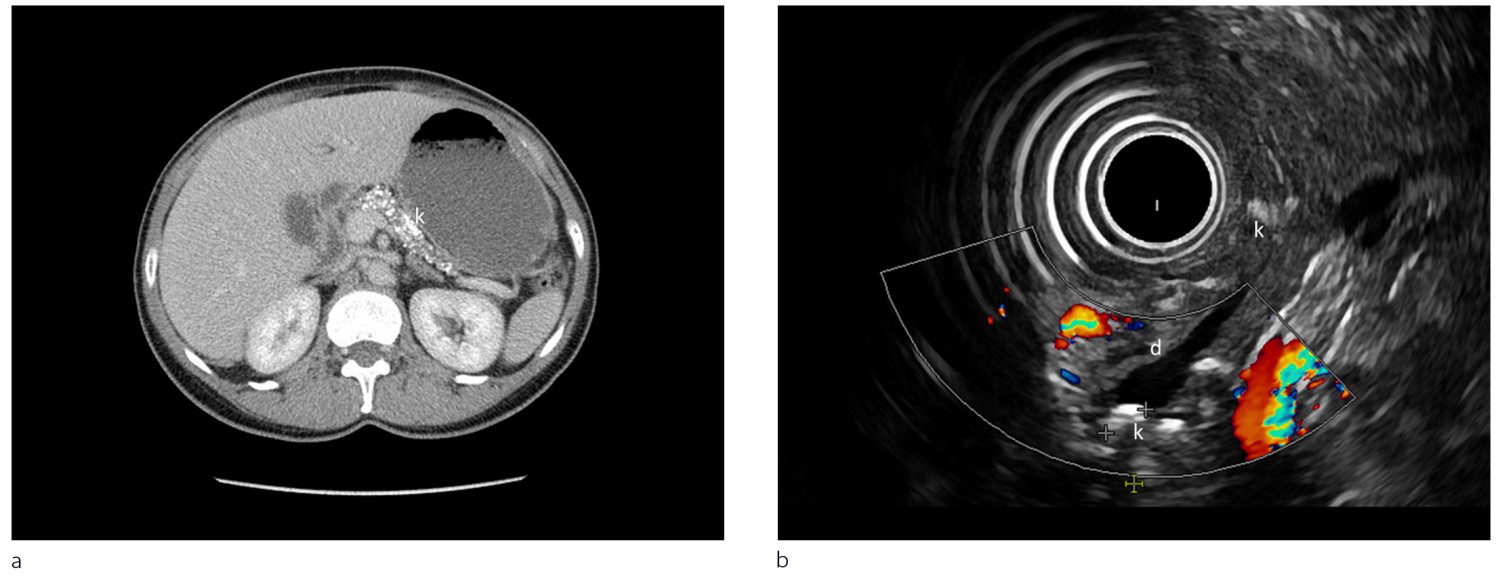

Radiologiske modaliteter som computertomografi (CT), magnetisk resonanstomografi (MR) og endoskopisk eller ekstern ultralydundersøkelse brukes til å påvise forandringer ved kronisk pankreatitt. Ved milde forandringer er endoskopisk ultralyd den mest sensitive metoden (1, 2). Fordeler og ulemper med de enkelte metoder med eksempler presenteres i figur 2 og ramme 3.

CT pancreas: CT-undersøkelse brukes i primærutredning og er gullstandard for å påvise forkalkninger ved kronisk pankreatitt. Undersøkelsen gjøres ved endring i symptombildet for å evaluere komplikasjoner som akutte pankreatitter, cyster, konkrementer eller malignitet

Endoskopisk ultralyd: Gir god fremstilling av gang- og vevsforandringer og er førstevalget ved tidlige kroniske pankreatittforandringer. Gir mulighet for biopsi av lesjoner i pancreas og tapping av pseudocyster